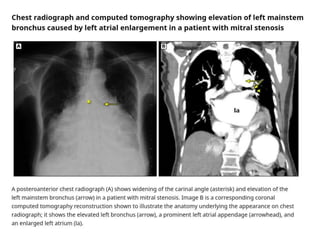

Chest X-ray

• The chest radiograph in mild MS may be normal,

although there is often evidence of some

enlargement of the left atrium and appendage

• Left atrial enlargement may produce the following

findings

• A "double density" (double right heart border

caused by the right side of the left atrium

extending behind the right cardiac shadow

• Straightened left heart border

• Elevated left bronchus

• On the lateral projection, posterior displacement of

the left atrium, impinging on the esophagus

Chest X-ray • Thechest radiograph in mild MS may be normal, although there is often evidence of some enlargement of the left atrium and appendage • Left atrial enlargement may produce the following findings • A "double density" (double right heart border caused by the right side of the left atrium extending behind the right cardiac shadow • Straightened left heart border • Elevated left bronchus • On the lateral projection, posterior displacement of the left atrium, impinging on the esophagus

• 23.